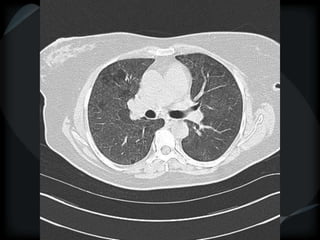

Emphysema - CL

Emphysema - PA

CL + PS emphysema